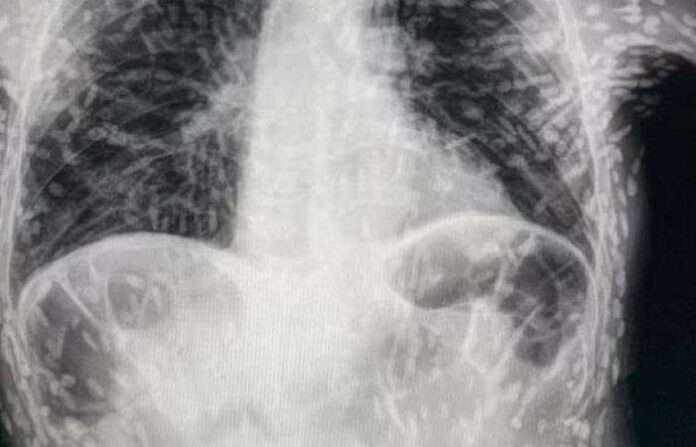

Bir doktorun Twitter’da paylaştığı röntgen, her biri bir parazitin yerleşmiş kalıntılarını temsil eden yüzlerce parlak lekeyi gösterdi.

Brezilyalı doktorlar, kendilerini şaşırtan bir vakanın röntgen görüntülerini paylaştı. İyileşmeyen öksürük ve baş ağrısı şikayeti olan hastanın uzun bir zamandır tenyalar tarafından tarafından organlarının delik deşik edildiği ortaya çıktı. Bilim insanları, parazit hastalıkların ölümcül olabileceğini belirterek, gıda hijyenine dikkat edilmesini istedi.

Görüntüyü paylaşan Brezilya’daki Botucatu’daki Hospital das Clínicas’tan Dr. Vitor Borin de Souza, hastanın öksürük şikayetiyle geldiğini ve durumun MRI ile rontgen taramalarında anlaşıldığını söyledi.